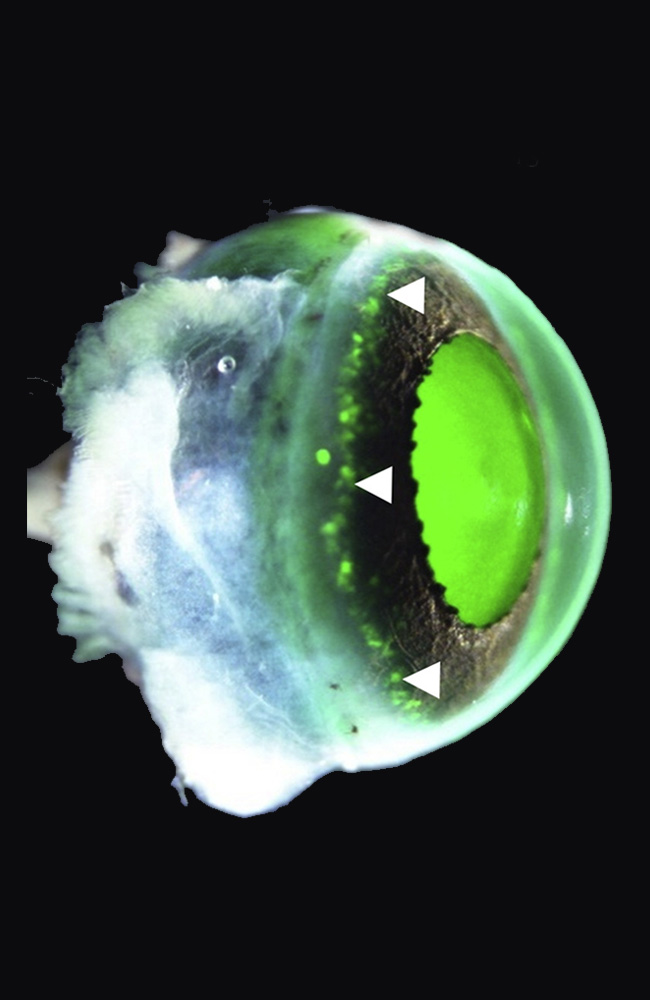

En 2024, el equipo del oftalmólogo Koji Nishida en la Universidad de Osaka anunció en The Lancet el primer ensayo clínico con láminas de epitelio corneal derivadas de iPSC alogénicas. Cuatro pacientes, cuatro ojos. La intervención consistía en trasplantar una capa de células corneales generadas a partir de un banco de iPSC compatibles con el sistema inmunitario de cada receptor.

El procedimiento era delicado. Las láminas, finas como un pétalo, se colocaban sobre la córnea dañada tras eliminar el tejido enfermo. A partir de ahí, el éxito dependía de la integración del nuevo epitelio, de su capacidad para mantenerse transparente y de no provocar rechazo.

Los resultados fueron tan sorprendentes como prudentes. En los cuatro pacientes, la superficie se reconstruyó de forma estable. La opacidad disminuyó, la inflamación se redujo y la agudeza visual mejoró. En uno de los casos, el efecto se mantuvo solo parcialmente al cabo de un año, lo que subraya la necesidad de seguimiento. Pero la seguridad del procedimiento quedó demostrada: ningún evento adverso grave, ninguna proliferación anómala, ningún tumor.

El proceso de fabricar un tejido ocular a partir de iPSC es una obra de precisión. Primero, se reprograman células somáticas —habitualmente de la piel— introduciendo una combinación de genes (los llamados «factores de Yamanaka») que las devuelven a su estado embrionario. Luego, mediante señales químicas y ambientales, se guían hacia un linaje concreto: en este caso, el epitelio corneal.

El resultado es una lámina de células vivas que, una vez implantada, se adhiere al estroma de la córnea y comienza a funcionar como barrera transparente y protectora. Es un proceso que combina biología molecular, ingeniería de tejidos y cirugía reconstructiva de alta precisión.